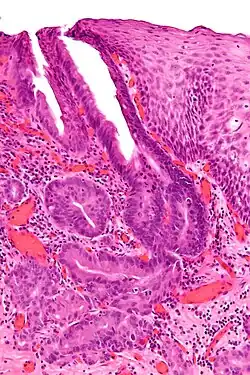

H&E stain of esophageal adenocarcinoma